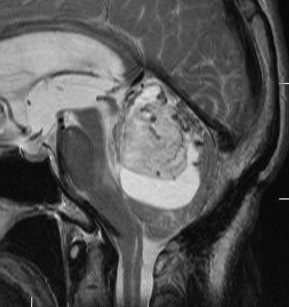

簡単な手術となる例

左右の写真は異なった患者さんのものです。両者ともに,大きな嚢胞(水たまり)を伴う小脳内部の小さな血管芽腫です。右の方に小さく白い塊(黄色の矢印)が見えるのですが,それだけが腫瘍で,濃い灰色に見える部分はのう胞といって液体がたまっているだけです。

これはとても(といっては何ですが比較的に)簡単な手術例です。小脳失調によるふらつきや水頭症よる頭痛と嘔吐などを出しますが,手術後に症状は改善します。

一般に小脳半球という場所にできたものは大きくても手術の成功率はとても高いです。小さいものでは場所と症状によってはガンマナイフなどの放射線治療も有効なことがあります。しかし,手術で摘出できるものは摘出した方が確実に治ります。